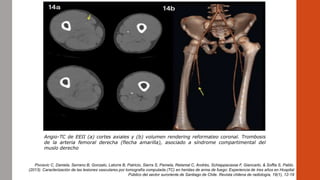

Angio-TC de EEII (a) cortes axiales y (b) volumen rendering reformateo coronal. Trombosis

de la arteria femoral derecha (flecha amarilla), asociado a síndrome compartimental del

muslo derecho

Pivcevic C, Daniela, Serrano B, Gonzalo, Latorre B, Patricio, Sierra S, Pamela, Retamal C, Andrés, Schiappacasse F, Giancarlo, & Soffia S, Pablo.

(2013). Caracterización de las lesiones vasculares por tomografía computada (TC) en heridas de arma de fuego: Experiencia de tres años en Hospital

Público del sector suroriente de Santiago de Chile. Revista chilena de radiología, 19(1), 12-19

Angio-TC de EEII(a) cortes axiales y (b) volumen rendering reformateo coronal. Trombosis de la arteria femoral derecha (flecha amarilla), asociado a síndrome compartimental del muslo derecho Pivcevic C, Daniela, Serrano B, Gonzalo, Latorre B, Patricio, Sierra S, Pamela, Retamal C, Andrés, Schiappacasse F, Giancarlo, & Soffia S, Pablo. (2013). Caracterización de las lesiones vasculares por tomografía computada (TC) en heridas de arma de fuego: Experiencia de tres años en Hospital Público del sector suroriente de Santiago de Chile. Revista chilena de radiología, 19(1), 12-19